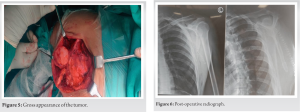

The patient was diagnosed with two ventral osteochondromas located on the body of the left scapula, with one positioned at the posteromedial border and the other proximal to the inferior angle of the scapula. Considering the patient’s cosmetic concerns, a surgical excision was proposed as the treatment approach. The excision procedure was carried out under general anesthesia (Fig. 5).

The surgical technique involved positioning the patient in a prone position. The shoulder was internally rotated to elevate the medial border of the scapula away from the thoracic cage. A parascapular incision was made along the medial and superior border of the scapula. A muscle-splitting approach, involving the trapezius and rhomboid muscles, was employed. No transverse incisions were made in any of the muscles to ensure a quicker post-operative recovery without compromising functional abilities. The osteochondromas were completely excised, and a post-operative X-ray was performed to assess the surgical outcome (Fig. 6). Following the surgery, the patient’s arm was immobilized in an arm pouch splint for a period of 3 weeks to ensure adequate rest. On the day after the surgery, the patient was allowed to engage in pendulum exercises as tolerated. Subsequently, the patient was referred to a rehabilitation program aimed at improving shoulder range of motion. During the course of rehabilitation, it was observed that the functional range of motion of the left shoulder was comparable to that of the unaffected side. The patient reported being free of pain and exhibited no signs of scapular winging. At the 1-year follow-up, the patient remained symptom-free, and there was no evidence of recurrence.